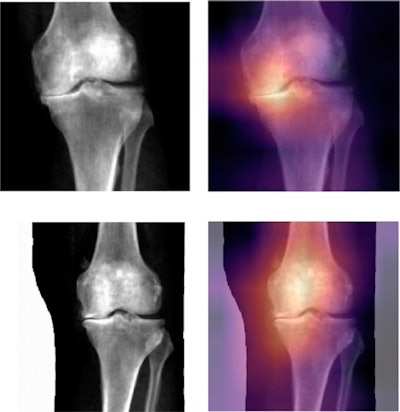

Grad-CAM interpretation of deep-learning-binary predictions. Grad-CAM heat mapping showing areas of highest activation for a control and case prediction made on the knee DEXA images. The regions of the map with the darkest color (purple) represent areas that were less informative in the prediction, while lighter colors (yellow) indicate regions of the image that informed the "case" or "control" prediction the most. We find areas of highest activation are most often on the medial side of the knee joint. Image courtesy of npj Digital Medicine through CC BY 4.0.The researchers then trained the AI model to identify these image-based phenotypes on a separate dataset of 546 images that had been independently annotated by three board-certified orthopedic surgeons. Next, in a test dataset of 110 images, the deep-learning model identified the imaging phenotypes with a sensitivity of 82% compared with clinicians (77%) and a specificity of 95% compared with the clinicians (97%).